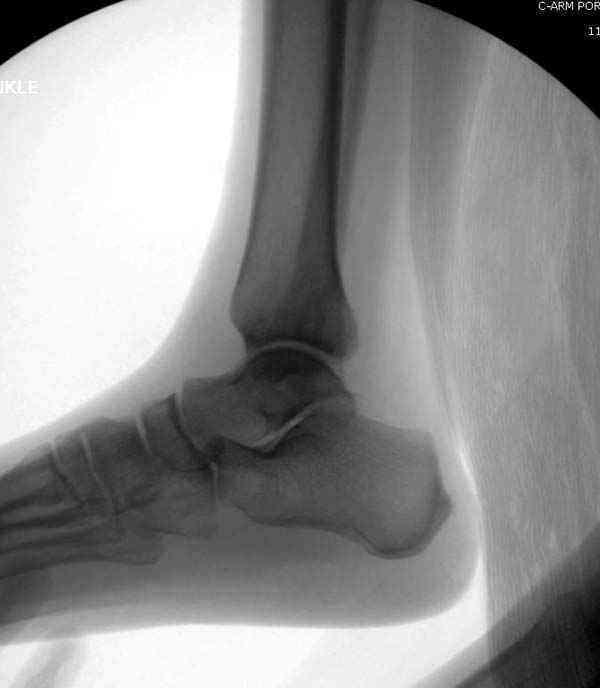

Нет первичных снимков, перелом очень низкий и под большим сомнением диагноз разрыва синдесмоза. Медиальная сторона отрепонирована на "хорошо" и, по-видимому, прорезание проволоки произошло во время операции. Без снимков трудно судить о высоте малоберцовой, а лодыжка находится в варусе. Лагирование получилось, но возле тонких шурупов передне-задний шуруп выглядит немного тяжеловато.

Здесь несколько частных случаев: перелом голеностопа со сравнительными снимками и разрыв синдесмоза, а также медиальная Hook пластина.